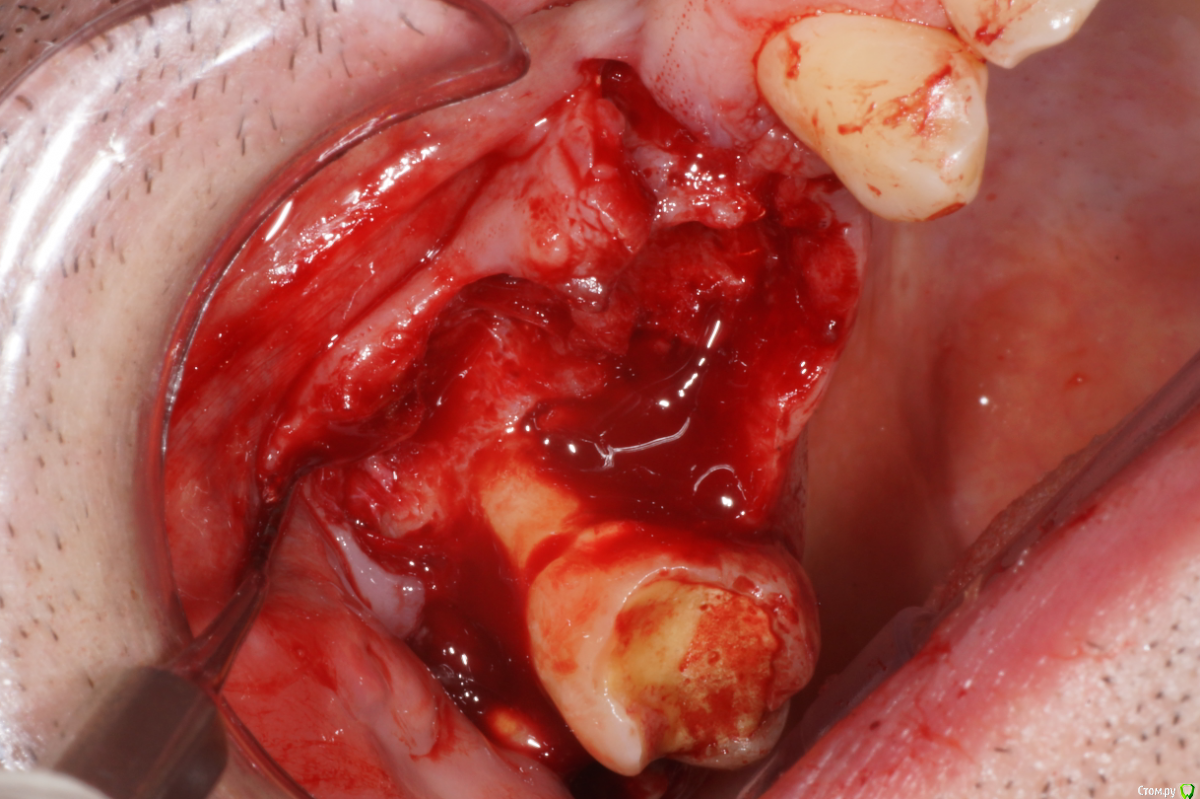

Я сначала решил, что в пазухе новообразование. Посмотрев внимательнее подумал что корень. Оказалось нечто среднее - недоформировавшийся корень, вросший в стенки пазухи.

В день вмешательства обрадовала ассистент - оказывается заказ "открытый синус лифт" еще не предполагает заказа на комплект гладилок. Сетевые клиники такие сетевые. Пришлось дедовским способом - турбинка, серповидная и распатор.

Ах да, забыл совсем. Удалил по ходу действия 1.8, обратите внимание на пазуху по КТ - септа в проекции 1.7 так удачно отделила отекшую слизистую от области синуса)